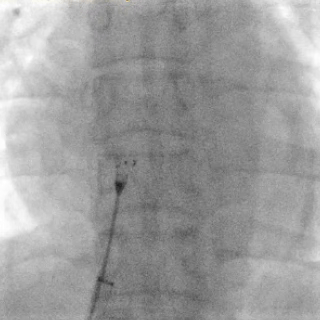

释放封堵器

DSA下封堵器完全释放后形态

封堵器释放后双盘紧贴间隔